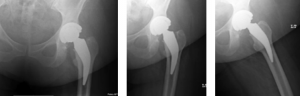

A 62-year-old African American male weighing 185lbs diagnosed with osteo/degenerative arthritis received Advita’s Alte on Neck Preserving stem with a Biolox® delta femoral head and InteGrip® acetabular shell. The patient underwent general anesthesia using a direct anterior surgical approach with an incision size of 9cm. There was an estimated blood loss of 200cc and surgery duration was 30minutes. The patient was discharged the same day as the operation with a walker to in home care for rehabilitation.

Pre-Op AP Pelvis

Harris Hip Score 48 (max=100) | Oxford Hip Score 19 (max=48)

6-Week Post-Op

Harris Hip Score 96 (max=100) | Oxford Hip Score 38 (max=48)

3-Month Post-Op

Harris Hip Score 89 (max=100) | Oxford Hip Score 44 (max=48)

1-Year Post-Op

Harris Hip Score 96 (max=100) | Oxford Hip Score 46 (max=48)

CONCLUSION

This patient presented with low Harris Hip and Oxford Hip scores before his total hip replacement. The direct anterior approach, which was used in this surgery, has been associated with faster functional recovery than the posterolateral approach. One year after surgery, his Harris Hip score increased by more than 50.0 percent, and his Oxford Hip score increased by more than 58.7 percent. The outcomes of his surgery continue to be followed each year, and the patient is satisfied with his total hip replacement. •